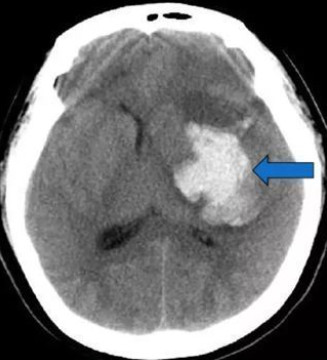

高血压引起的脑出血简称为高血压脑出血 , 发病年龄多发生于50-60岁有高血压病的患者 , 死亡率占非创伤性脑出血的首位 , 其发病快、死亡率高、恢复慢 , 常遗留有不同程度的神经功能障碍 。

一般来说 , 高血压脑出血的患者首先需要控制血压 。 2018年中国脑出血专家共识指出 , 在收缩压<220mmHg的情况下 , 数个小时以内降到140mmHg以下是安全的 。 还有一个就是大家关心的需不需要做手术的问题 , 人的大脑有小脑幕分为幕上和幕下 , 在通常情况下 , 患者存在意识障碍;幕上出血>30ml , 大脑中线偏倚>5mm;幕下出血>10mm;单侧瞳孔散大; 脑疝形成;没有其他手术禁忌症(心衰、肝肾功能严重衰竭)的情况下是手术指征 。 有的家属一听到脑出血就慌了神 , 全然不顾医生的沟通 , 就想着多打电话叫家属过来 , 殊不知这也是在拖延手术时机 , 一般来说6个小时以内做手术是时机比较理想的时候 。